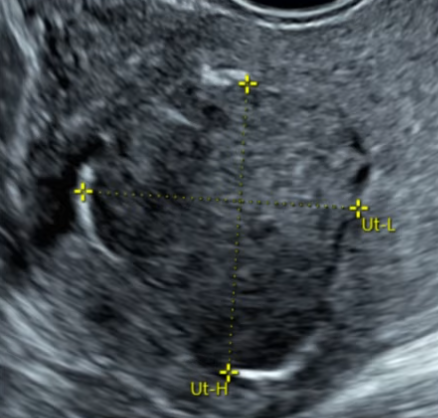

肌瘤类型和位置经评估适合做USgFUS。